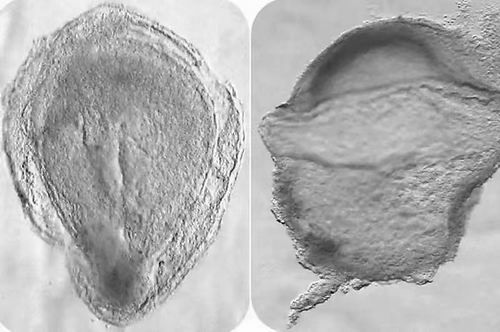

图片来源:Srinivas, Scialdone

英国牛津大学的Shankar Srinivas和同事分析了一个在自愿终止妊娠后被捐赠用于研究的人类胚胎,该胚胎所处的阶段相当于受精后的第16至19天。

研究人员对胚胎中的细胞类型和这些细胞表达的基因进行了详细的描述,并与实验模型进行了对比。研究人员最终检测到了原始生殖细胞(成为卵子或精子细胞的干细胞)和红细胞等等。

他们还发现,神经系统的细胞特化在这个发育阶段尚未开始。